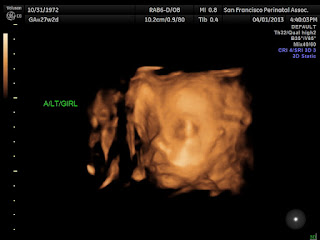

The 27 week ultrasound was just a routine visit. They said that the girl had a 150 BPM heart rate and was measuring at 2 lbs. 5 oz. The boy measured at 140 BPM and 2 lbs. 4 oz. That's nearly 5 pounds of baby growing in me. Someone having a singleton would experience this much baby weight at 32 weeks of pregnancy.

Here are a few blurry photos for you to enjoy. Remember, when the picture says A, that is the girl, and B is the boy. The last photo is their two little heads together.